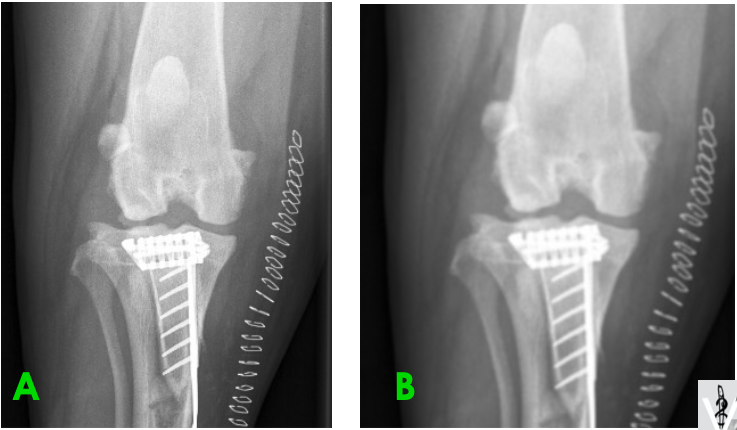

Laquelle des 2 radiographies a été prise avec un filament de taille plus petite?

B : on y voit mieux les rebords osseux. Ici, c’est une partie du corps immobile et on peut se permettre d’augmenter le temps afin de diminuer le mA et donc le filament.

La taille du filament affecte le mA : plus petit = mA plus bas

À mAs équivalent : temps augm, mA diminue => permet d’avoir une meilleure netteté